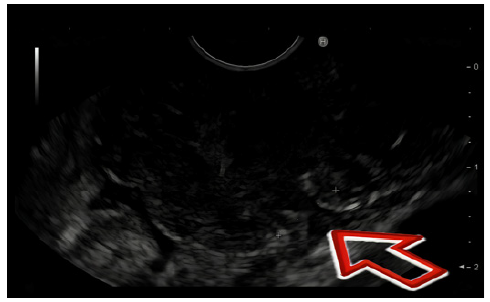

A 58-year-old female, with a medical history of stage IIB Hodgkin lymphoma in remission for over 5 years post-chemoradiation, and treated invasive breast and renal carcinomas, was incidentally diagnosed with a cardiac gastric polyp on a follow-up computed tomog-raphy (CT). Upper endoscopy and endoscopic ultrasound (EUS) revealed a 50 mm ulcerated polypoid subepithelial lesion (Fig. 1) originating from a small stalk in the muscularis propria (MP). Biopsies and fine-needle biopsy were inconclusive but without epithelial neoplastic tissue. Subsequent staging showed no lymph nodes or distant metastasis. Given the high morbidity associated with surgery - total gastrectomy - the tumor’s small insertion in the MP, the patient’s lack of lymph node involvement or distant metastasis, and their preference for a less invasive approach, endoscopic submucosal dissection (ESD) was chosen as the optimal treatment option. En bloc ESD was performed without technical difficulties, revealing the lesion’s superficial origin in the MP (Fig. 2), which eliminated the need for perforation and subsequent defect closure. However, because of its dimension and shape, the specimen was fragmented during retrieval. Histological analysis confirmed gastric leiomyosarcoma with non-evaluable margins (Fig. 3). Following multidisciplinary discussion, surveillance was recommended. At 12-month follow-up, the patient remains with no signs of recurrence at CT and endoscopic evaluation.

Imaging diagnosis is often achieved using CT scans and EUS, which are valuable tools in evaluating these cases, specially the latter one as it enables the sampling of deeper tumor tissues with ultrasound-guided fine-needle aspiration. However, as demonstrated in our case, distinguishing leiomyosarcomas from other gastric tumors with these methods can be challenging. Endoscopic biopsies are also frequently ineffective due to the submucosal origin of the lesion. Smooth muscle tumors, including leiomyoma and leiomyosarcoma, typically show positivity for smooth muscle markers such as actin, desmin, and h-caldesmon, while they are generally negative for c-kit (CD-117) and CD-34 [3].